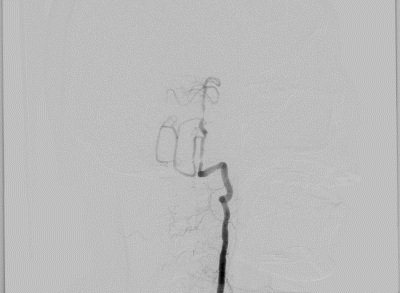

DSA提示:双侧颈内动脉及颅内血管未见明显狭窄,右侧椎动脉优势,左侧椎动脉纤细,V4段闭塞。右侧椎动脉起始处重度狭窄,右椎V4段及基底动脉近端局限性重度狭窄。患者反复间断发作头晕,考虑后循环缺血引起的TIA发作,且强化药物治疗效果不佳,有介入治疗适应症。

全麻后,股动脉置入6F血管鞘,6F导引导管配合超滑导丝至右侧锁骨下动脉建立通路,Synchro-14(200cm)微导丝配合4mm×30mm快交球囊定位V1狭窄扩张。

6F导引导管进入V2后,Synchro-14 (200cm)微导丝配合Gateway 2.5mm×9mm球囊先后进行基底动脉、椎动脉V4段狭窄扩张。

撤出球囊后,Synchro-14(200cm)微导丝配合XT-27至基底动脉远端,从远至近分别置入Neuroform EZ 3mm×15mm及Neuroform EZ 3.5mm×20mm支架。

最后保留微导丝在椎动脉内,将导引导管退至锁骨下动脉后,送入5mm×19mm球扩式支架并释放。